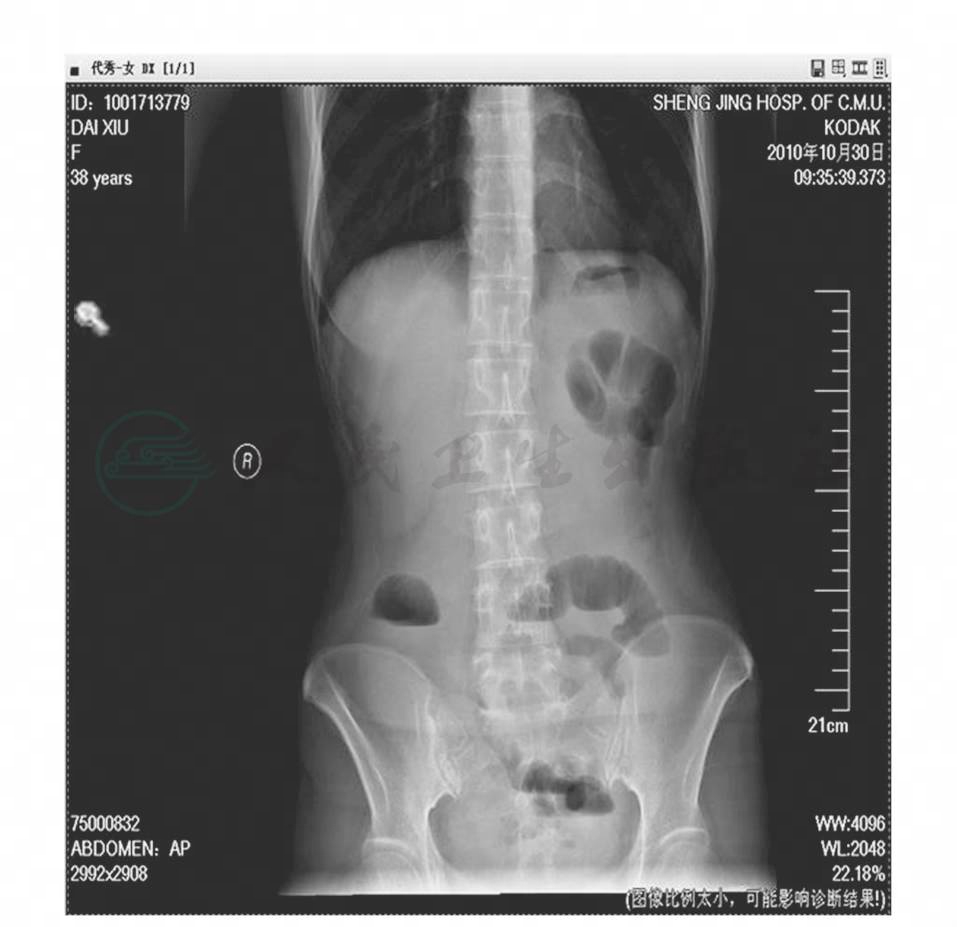

腹部平片(2008-10-26):腹部部分肠管可见积气,其内未见气液平面影(图1)。

图1 腹部平片